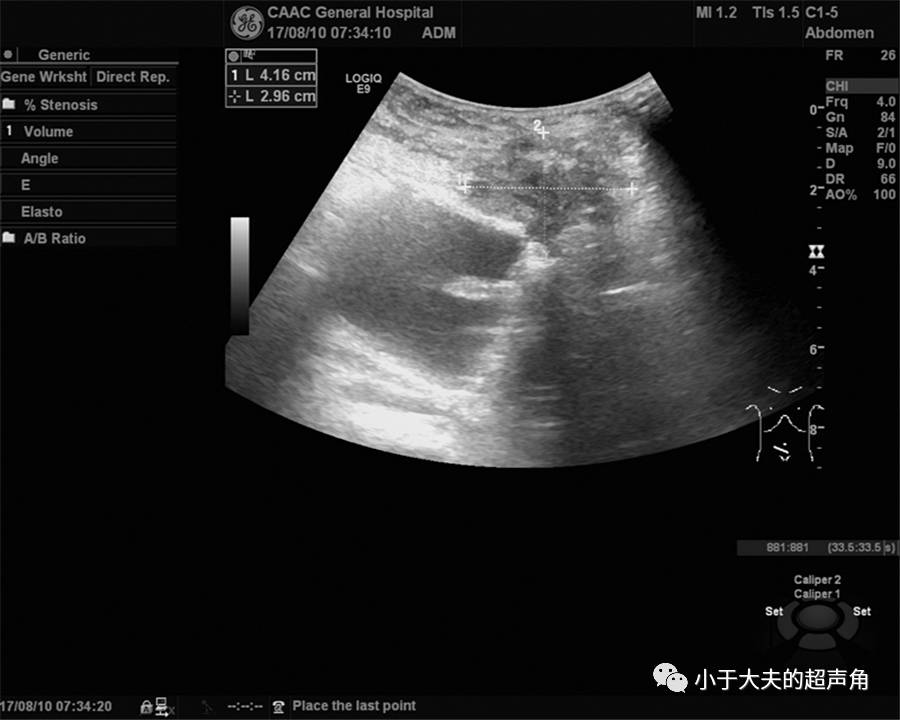

上图:检查时,发现多处肠管扩张,较宽处4.1cm,考虑存在梗阻。在梗阻肠管远端及周边仔细探查,以期发现更多异常之处。